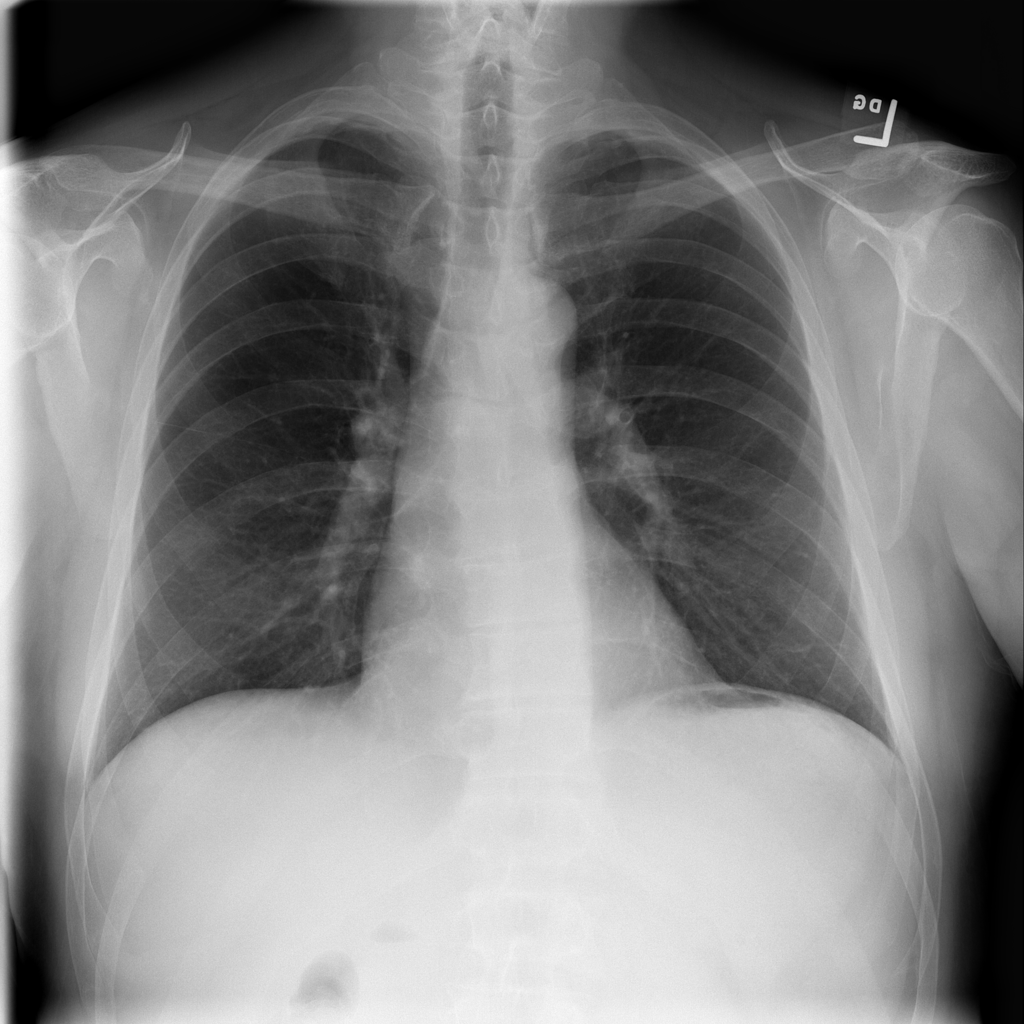

PAT-1F50 · IMG-000Fibrosis

PAT-1F50 · IMG-000

PA